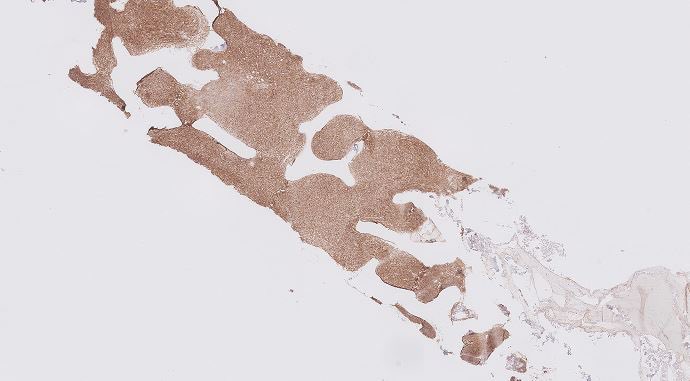

Illustration of a case of Burkitt lymphoma in the intestine with characteristic variable/ patchy SOX11 expression pattern. SOX11 may come in handy in tricky cases when you need more evidence to push for Burkitt lymphoma vs other mimickers #hemepth #lmsm #pathtwitter #PathX #MedX

SibaElHussein's tweet image. Illustration of a case of Burkitt lymphoma in the intestine with characteristic variable/ patchy SOX11 expression pattern. SOX11 may come in handy in tricky cases when you need more evidence to push for Burkitt lymphoma vs other mimickers #hemepth #lmsm #pathtwitter #PathX #MedX